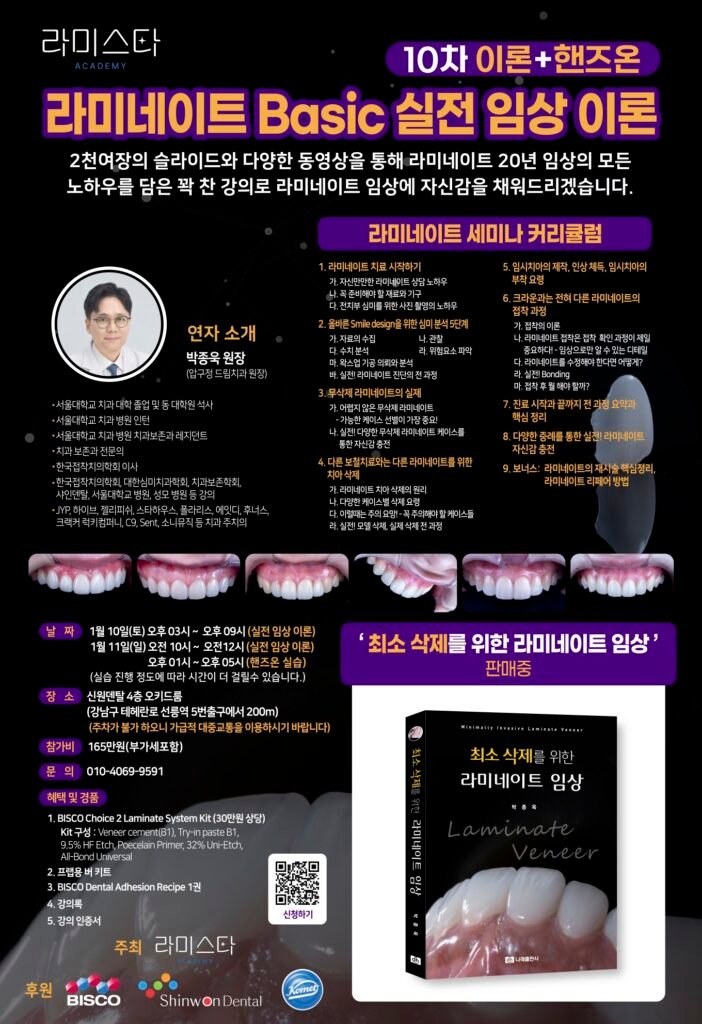

Over 27 years of clinical experience by Dr. Jonguk Park at Dream Dental Clinic in Apgujeong.

Dream Dental Clinic(드림치과)은 2006년부터 압구정동에서

**자연스러운 라미네이트(Laminate Veneer)**를 전문으로 해왔습니다.

박종욱 원장은 1998년부터 27년 넘게 임상에 집중하며

수많은 라미네이트 강의와 교과서를 통해

한국 심미치과의 기준을 만들어 왔습니다.

Dr. Jonguk Park은 27년의 임상 경험을 바탕으로

치아의 생리적 구조를 최대한 보존하며,

자연스러운 투명감과 깊이감이 살아 있는 라미네이트를 추구합니다.

Dream Dental Clinic은 빠름보다 정확함을,

양보다 정성을 중요하게 생각합니다.